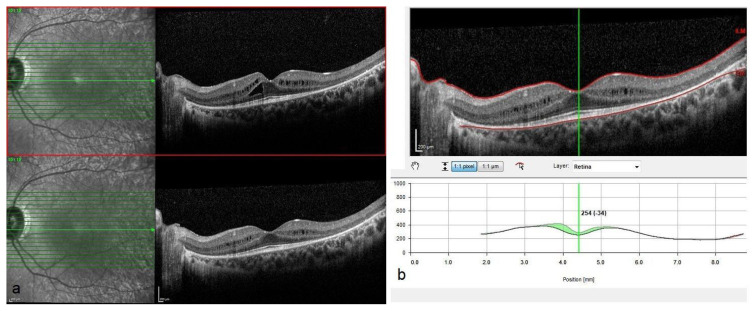

Background/aim: To evaluate the short-term efficacy and safety of nondamaging retinal laser therapy (NRT) for retinitis pigmentosa-associated cystoid macular edema (RP-CME) and analyze anatomical and functional outcomes.

Materials and methods: A retrospective case series of 40 eyes from 30 patients with RP-CME was conducted. The patients underwent NRT using a PASCAL laser system with endpoint management (EpM) software. Central macular thickness (CMT) and best-corrected visual acuity (BCVA) were assessed at baseline and 2 months posttreatment. Long-term follow-up data, including recurrence rates were also reviewed.

Results: At the 2-month follow-up, NRT significantly reduced mean CMT by 79.7 μm (p < 0.001) and improved BCVA by 0.10 LogMAR (p < 0.001). Complete resolution of CME was observed in 30% of the eyes, while 52.5% experienced recurrence within 6 months. Unilateral cases exhibited greater CMT reductions than bilateral cases (p < 0.05). No retinal damage from the laser was observed. The long-term sustainability of these effects remains unclear, and repeated treatments have not yet been assessed.

Conclusion: NRT is a safe and effective short-term treatment for RP-CME, achieving significant anatomical and functional improvements without evidence of retinal damage. However, the high recurrence rate and absence of long-term data warrant further investigation. Future studies should explore repeated treatments, genetic subtypes, and correlations with the ellipsoid zone integrity.